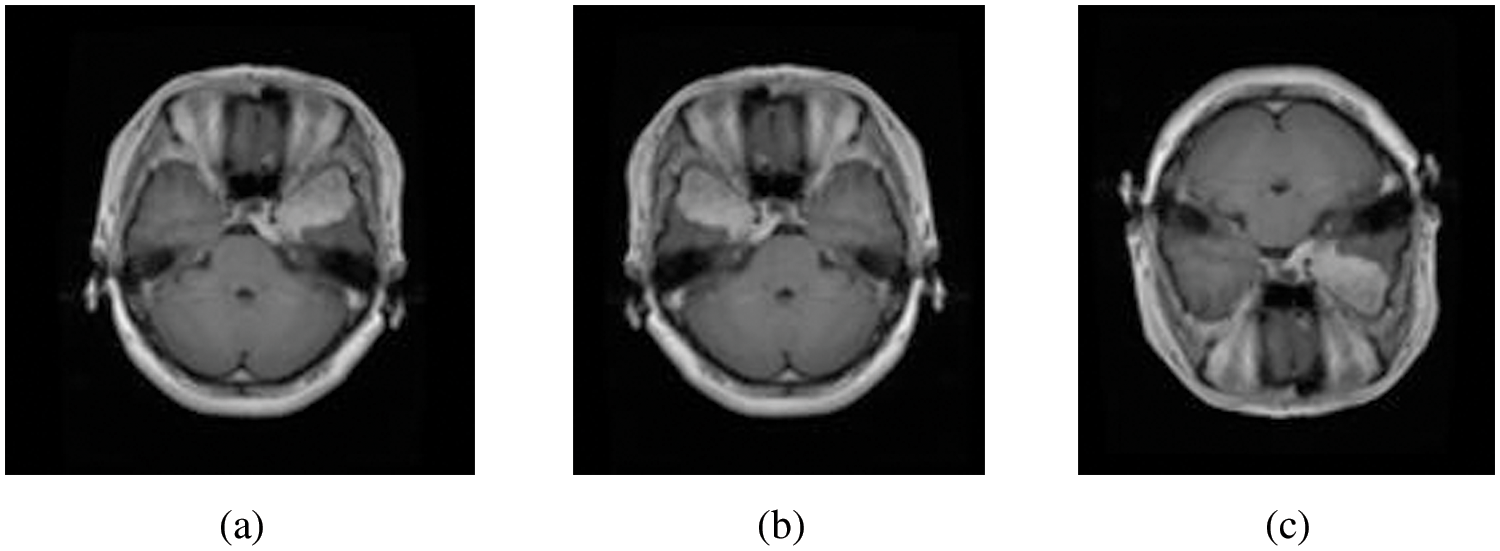

The presented study has been built based on two standard MRI datasets, a multi-class dataset and a binary one. The first dataset captures from Nanfang Hospital and General Hospital, Tianjin 107 Medical University, China, between 2005 and 2007. It was published online in 2015 [16], and the most recent 108 revisions were completed in 2017. This dataset contains three different cases of brain tumors, including (meningioma, glioma, and pituitary) and no tumors. All MRI images have been acquired from three different views: axial (994 images), coronal (1045 images), and sagittal (1025 images) views [17]. On the other side, the second dataset can distinguish between equally healthy and tumor cases to form a 3000 MRI images dataset [18]. Fig. 3 refers to the sample of the different applied datasets, and the detailed datasets have been tabulated in Table 1.

Figure 3: Sample of both Datasets (a) Multi-class MRI and (b) Binary MRI